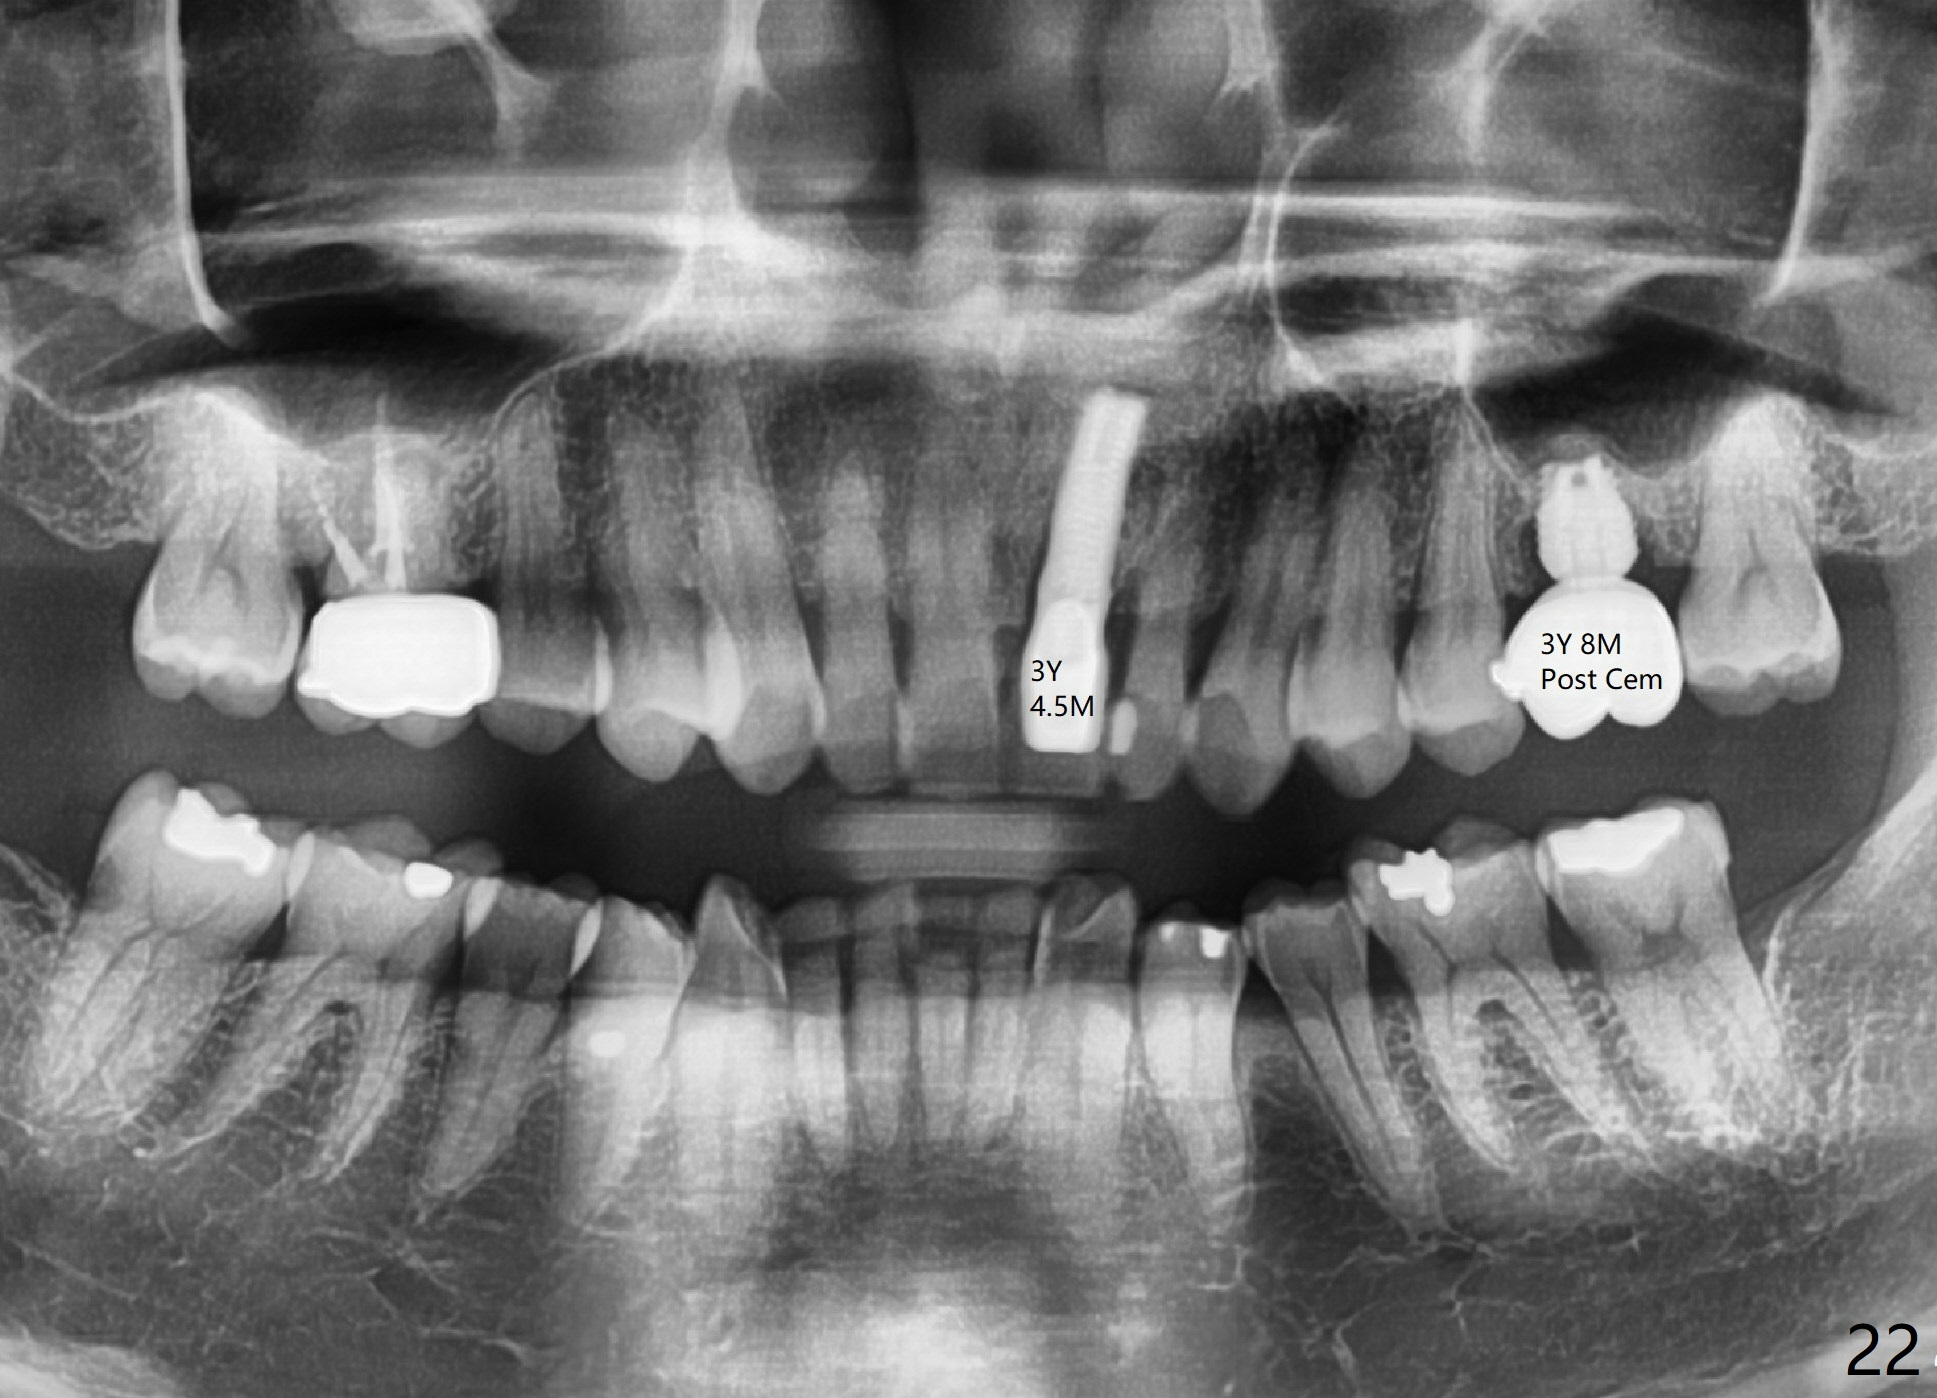

A 45-year-old man has lost the tooth #14 for a while (Fig.1); bone height is 5.4 mm. An extra wide and short implant is planned. Torus palatinus is large, suggesting that bone density should be high. A 6 mm tissue punch is chosen, but it is placed more palatal. If it were placed in the middle of the ridge, there would be no buccal keratinized gingiva (incision may avoid this issue). Additionally, the buccal portion of punch is made incomplete so that there is pedicle on the buccal side when the flap is raised (Fig.4,8: F). It is expected that the excess portion of keratinized tissue will form thick gingiva buccally. Osteotomy proves that bone is dense (Fig.2 (4.5x11 mm tap). Typical sinus lift is finished with placement of 6.4x6 mm (extra wide) bone-level implant (Fig.3, >55 Ncm). Following further torque, Fig.4 shows that the implant (I) is sub-gingival (<). Bitewings are taken to confirm that the implant plateau is at the crestal level (Fig.5,6 ^). PA shows sinus lift (Fig.7 *). The lingual aspect of the implant and healing abutment (H) is further bone grafted and covered by collagen dressing (Fig.8 *). The wound is protected with perio dressing. When the latter dislodges 7 days postop, the collagen dressing and bone graft are lost as well (Fig.10), while the buccal flap remains vital (Fig.9). The lingual exposed plateau should be able to heal normal. The collagen dressing should have been fixed in place by suture or as simple as a dental floss. There is mild nasal hemorrhage 1-2 days postop, possibly related to sinus membrane perforation and inability of Collagen Dressing to cover the perforation and contain the bone graft. When the patient returns for #9 implant placement in 3 weeks postop, the buccal flap reduces in size (Fig.11 *), while the palatal wound has healed with minimal exposure of the implant (Fig.12). Sinus graft remains in place 3 months postop (Fig.13); the buccal flap appears to have incorporated into a part of the gingiva (Fig.14). The bone density of the sinus lift appears to increase 10 days later when an abutment is placed (Fig.15 *). Although oral hygiene is pristine, there is apparent crestal bone resorption 12 months (Fig.16) and 20 months (Fig.17) post cementation, probably due to unfavorable crown/implant ratio and bruxism as well as pre-implantation bone loss (Fig.18,19). In contrast, an immediate implant in the same patient avoids pre- or post-implantation bone loss. In fact both the soft (Fig.20) and hard (Fig.21) tissues remain healthy 2 years 8 months post cementation. The sinus lift remains 3 years 8 months post cementation (Fig.22), while the crestal bone loss persists. The patients keeps complains of food impaction distal associated with bad smell 4 years 1 month post cementation. In fact the distal proximal contact is within normal limit. The bad smell is probably due to crestal bone loss (Fig.23 (pan), 24 (CT) *) and periimplantitis. Bone graft, PRF and Cytoplast membrane will be needed and fixed in place with long healing screw. When the patient returns for crown redo, he also reveals floss related gingival hemorrhage. There is pain associated with palatal sulcus probing with light gingiva erythema. Review of CT coronal section shows possible palatal (Fig.25 P) bone loss (*).